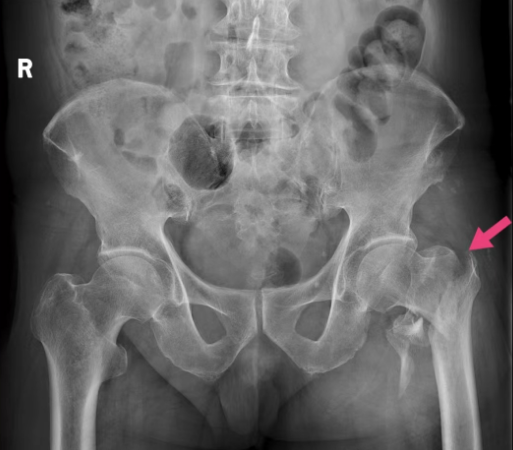

4月24日,86岁的肖爷爷在家不慎滑倒,左侧身体着地,左髋部剧烈疼痛不能活动,家属立即拨打120急救电话送往医院急诊科,急诊检查诊断为“左侧股骨粗隆间骨折、脑梗死后遗症、高血压、双侧膝关节炎”。骨科医生石博接诊后立刻上报医务部,当即对患者开放了绿色救治通道快速完成各项检查,运用多学科联合诊疗MDT工具,入院当日即完成了麻醉科、神经内科、心内科、ICU等多个相关学科的会诊支持,一致同意为患者实施手术,尽快摆脱骨折-卧床-基础病及合并症进行性加重-死亡的恶性循环,最大程度提高患者的生存率。当时肖爷爷和家人犹豫不决,不手术的话疼痛和活动不便难以忍受,而手术又担心年纪大合并症多导致手术风险大,难以抉择。经过骨二病区沈其孝主任和连一医援阳骨科副教授霍永峰的耐心沟通,反复权衡利弊后最终决定积极手术治疗。

手术切口和术后图片(右图红色线条示意微创手术切口)

患者和家属同意手术后,在医院多学科努力下,克服患者长期口服氯吡格雷等抗凝药物等困难,在伤后2天内通过髂筋膜阻滞复合麻醉和微创手术的方法,为患者实施了骨折闭合复位髓内针内固定手术,手术仅有两个长为3cm的切口,出血约为50ml。术后通过ICU病房监护调整,手术次日患者即转入普通病房并开始在保护下站立负重训练,摆脱了卧床状态。既往这种高风险高龄患者常需调整5-7天后方能手术,术后由于心肺功能和肌力的下降,康复效果也要打一个大的折扣。为改善预后,提高疗效,阳新县人民医院积极响应国家卫健委号召,推动开展老年髋部骨折的多学科诊疗工作,促进老年患者的加速康复,肖大爷是其中一个典型示例。